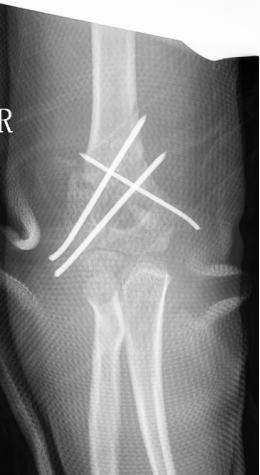

4、小黄(化名):男、6岁、在家里从椅子上摔下致右肘部肿痛、畸形、活动受限3小时就诊我院。(下图为患儿术前X线片)

麻醉下手法整复经皮钢针内固定,术后患儿恢复良好。(下图为患儿术后X线片)